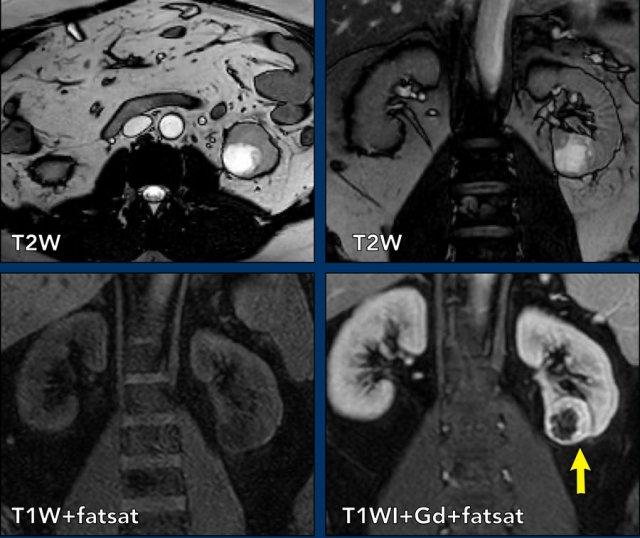

Ca lâm sàng 1

Các hình ảnh cho thấy một nang thận phải phức tạp kích thước lớn với dịch bên trong tăng tín hiệu trên cả chuỗi xung T1W và T2W, cùng với cặn lắng tăng tín hiệu T1W, có ngấm thuốc nhẹ trên ảnh trừ (subtraction image).

Nang này còn có một nốt thành ngấm thuốc (xem mũi tên trên ảnh mặt phẳng coronal), phân loại đây là tổn thương Bosniak IV.

Thận đã được phẫu thuật cắt bỏ và nang được xác định là ung thư biểu mô tế bào thận dạng nhú.

Ca lâm sàng 2

Các hình ảnh cho thấy một khối dạng nang với thành dày (< 4mm) và một vài vách dày không đều.

Trên các ảnh sau tiêm thuốc tương phản từ, không ghi nhận ngấm thuốc của vách hoặc thành, nhưng có thể xác định rõ ràng một nốt thành ngấm thuốc (mũi tên).

Do đó, đây là tổn thương Bosniak IV. Tổn thương đã được phẫu thuật cắt bỏ và được xác nhận là ung thư biểu mô tế bào sáng (clear-cell carcinoma).

Ca lâm sàng 3

Các ảnh T2W mặt phẳng axial và coronal cho thấy một tổn thương dạng nang ở cực dưới thận trái với thành dày không đều.

Do thành phần mô đặc chiếm dưới 25% tổn thương, tổn thương cần được phân loại là khối dạng nang thay vì u thận đặc dạng nang.

Trên các ảnh T1W coronal có ức chế mỡ trước và sau tiêm thuốc tương phản từ, độ dày thành đo được trên 4 mm (mũi tên).

Tổn thương được phân loại là khối dạng nang Bosniak IV.

Khối đã được phẫu thuật cắt bỏ và được xác nhận là ung thư biểu mô tế bào sáng.